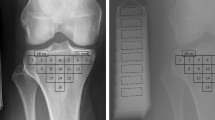

Machine learning was used for dimensionality reduction and to evaluate how well subjects without and with osteoarthritis can be distinguished using radiomics features from tibial bone. Three different models were used: (1) covariate model that included age and BMI that are two common risk factors for osteoarthritis [33], (2) image features model, and (3) combined covariate + image features model. Dimensionality reduction and classification were done using the Elastic Net regression, which is a regularized logistic regression method [34, 35]. The Elastic Net linearly combines the L1 and L2 penalties of lasso and ridge regression methods. To optimize the ratio of the L1 and L2 penalties (α) and the strength of the penalty parameter (λ) of the Elastic Net, 10-fold cross-validation with a grid search and 100 repetitions was performed. In the grid, the values of α varied from 0.1 to 1 with an increment of 0.05 and λ from 0.001 to 0.15 with an increment of 0.009. When α is close to 0, the Elastic Net approaches ridge regression, while when α is 1, lasso regression is performed. In cross-validation, the performance of the aforementioned three models to distinguish between subjects without and with osteoarthritis was assessed using the area under the receiver operating characteristic (ROC AUC) and precision-recall curves (PR AUC) along with 95% confidence intervals (CI) [36]. To assess the ability of radiomic features from medial tibial bone to distinguish individual osteoarthritis-related structural changes, analyses were repeated using medial tibial cartilage damage, osteophytes, and bone marrow lesions as an outcome variable. The Elastic Net experiments were done using the R software (version 3.5.2) with Caret [37], PRROC [38], glmnet [34], and precrec [39] packages.

When classifying knees without and with tibiofemoral osteoarthritis, ROC AUC and PR AUC of 0.80 (95% CI: 0.73–0.87) and 0.46 (95% CI: 0.33–0.58) were obtained with the model that combined image features from all VOIs and covariates (Table 2, Fig. 2). When each VOI was assessed separately, the medial subchondral bone VOI had the highest ROC AUC (Table 2). The model that combined image features from the medial subchondral bone VOI with covariates had an ROC AUC of 0.80 (95% CI: 0.72–0.87) and a PR AUC of 0.46 (95% CI: 0.33–0.58) (Supplementary Figure 1).